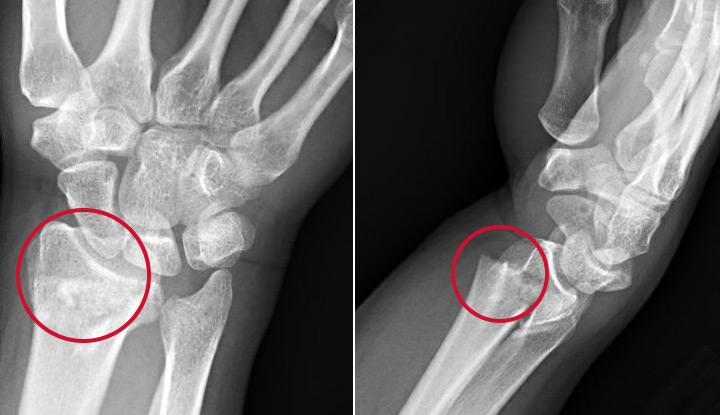

Colles Fracture Symptoms Causes Treatment